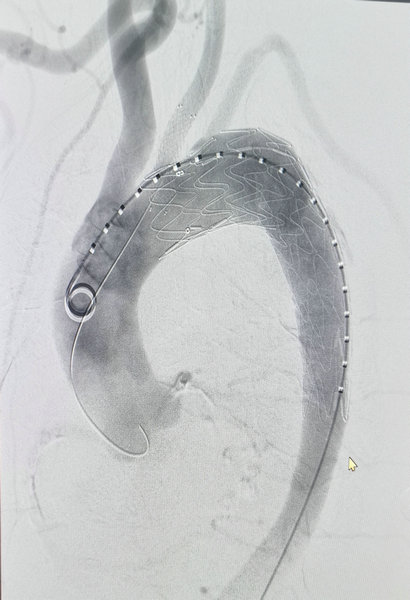

王颖主任与患者及家属充分沟通后,同意进行手术治疗。在麻醉科、介入科、ICU及透析室等多科室密切协助配合下,王颖主任及血管外科团队为患者行全麻下胸主动脉腔内隔绝联合左侧颈总动脉支架植入术,术中因患者血液透析多年,血管病变非常严重,稍有不慎就可发生动脉瘤破裂导致死亡,其手术风险较大,难度系数高,术中需要整体团队的紧密配合,更离不开麻醉科高雪松副主任精确地药物控制,经过王颖主任造影精确定位后,释放覆膜支架及颈动脉支架,再次造影破口封堵满意。术后患者意识逐渐清醒,在医护人员的悉心护理下,患者恢复良好,病情转危为安,达到了满意的效果,目前已康复出院。

血管外科王颖主任为患者行胸主动脉腔内隔绝联合左侧颈总动脉支架植入术

造影显示覆膜支架及颈总动脉支架已成功释放